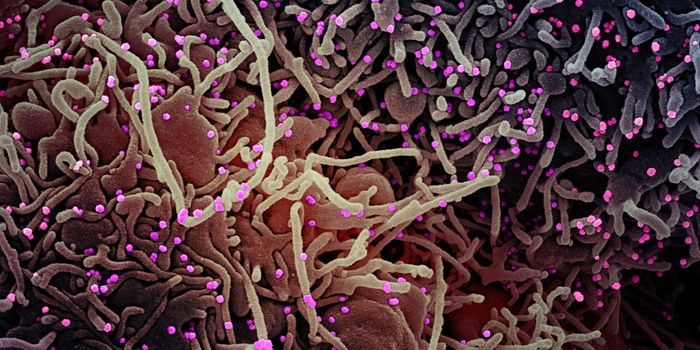

AUG 26, 2021MicrobiologyScientists have used a mouse model to visualize the progression of a SARS-CoV-2 infection as it led to sometimes fatal c ...